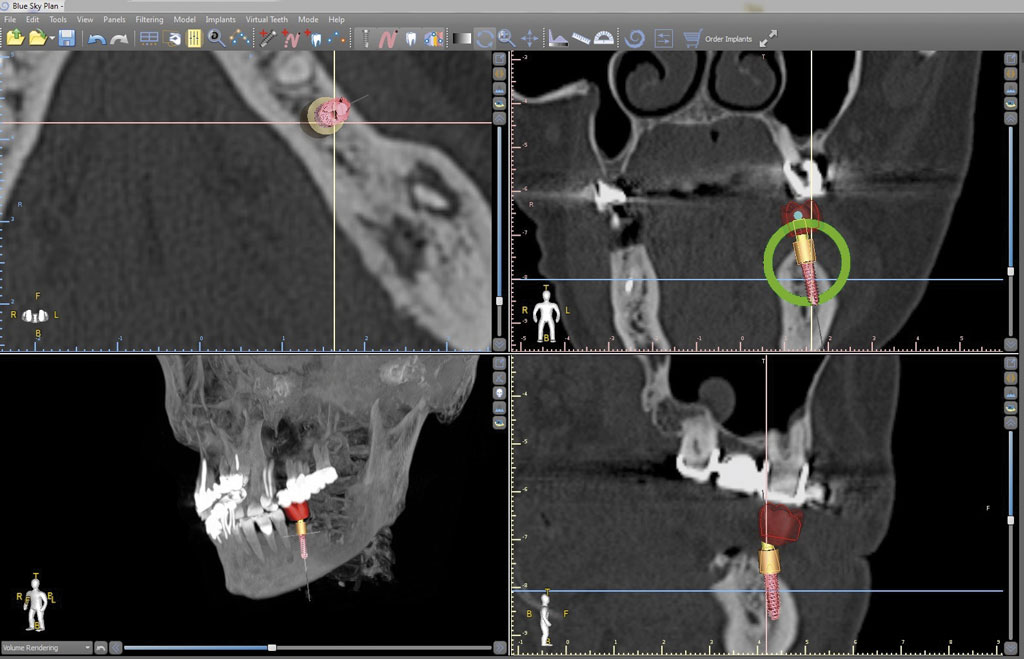

Praca zawiera podstawowe informacje dotyczące stomatologicznych szablonów implantologicznych. Autorzy omawiają rodzaje szablonów, procedurę wykonania, wyniki i powikłania związane z ich użyciem oraz czynniki wpływające na dokładność implantacji z ich zastosowaniem.

The study contains basic information regarding dental implant guides. The authors discuss types of templates, the procedure that is carried out, the results and complications associate with their use, together with the factors influencing the accuracy of implantation with their use.